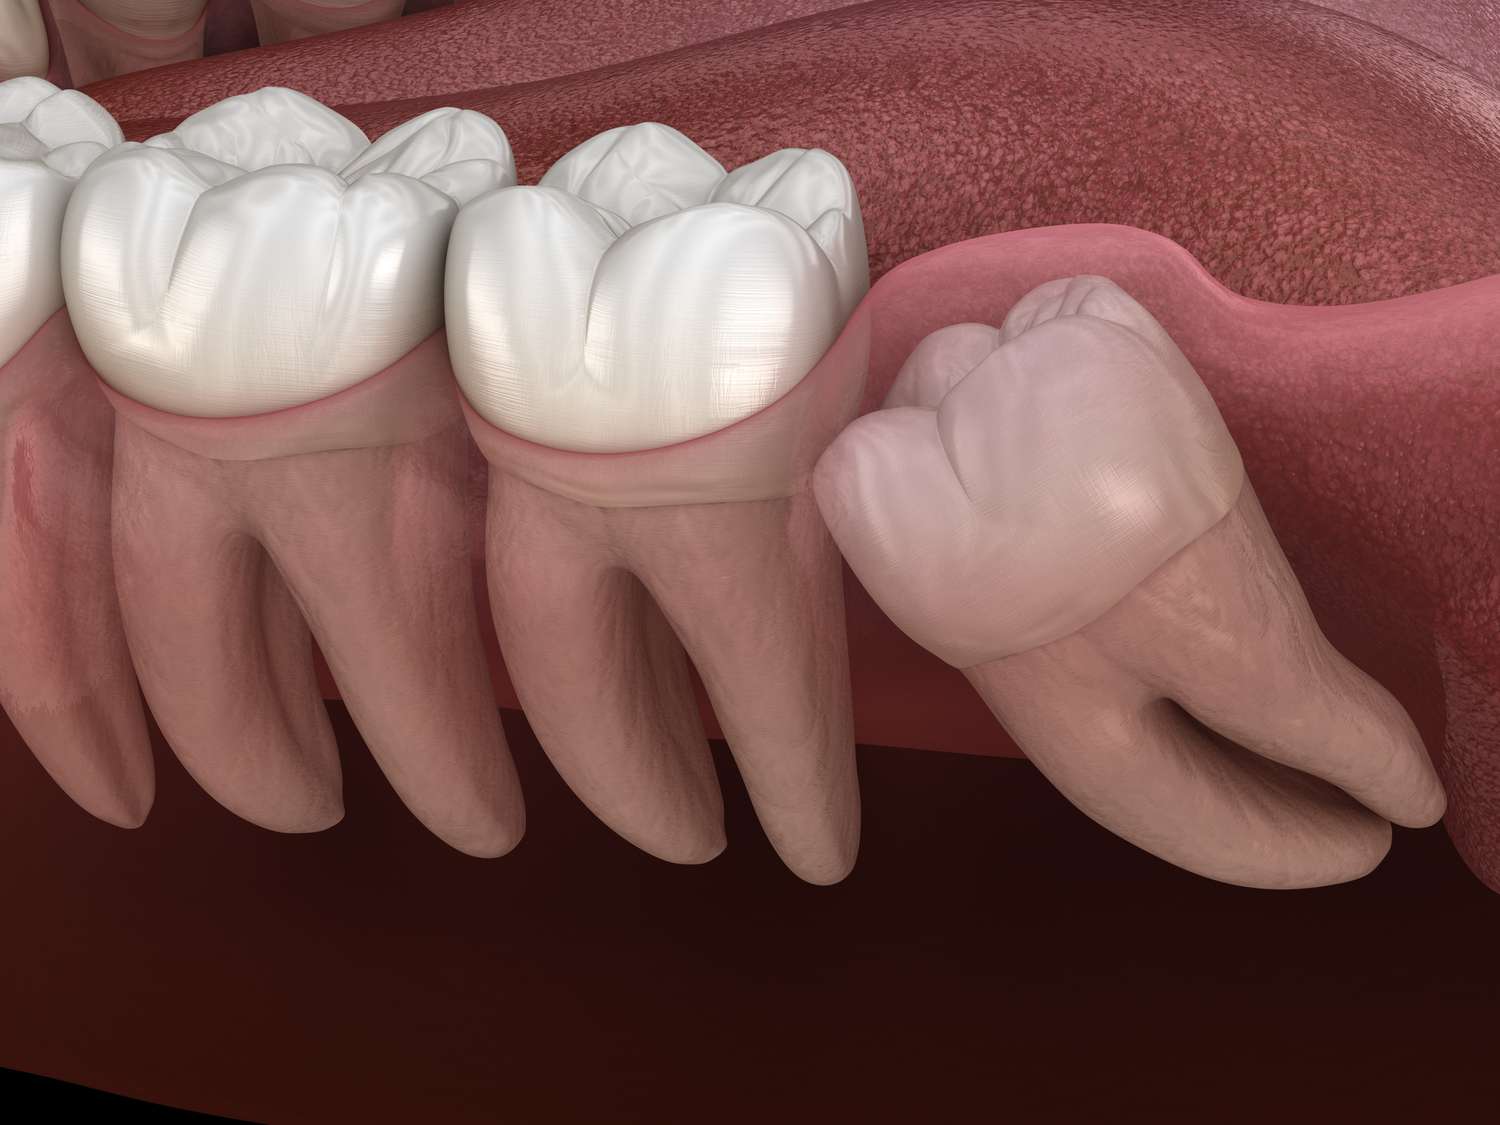

Extraction of impacted or partially erupted wisdom teeth.

- Extraction: Wisdom tooth surgery involves the removal of impacted or partially erupted wisdom teeth.

- Anesthesia: Patients receive local anesthesia or sedation to ensure a pain-free procedure.

- Incision and Removal: The surgeon makes an incision, removes the tooth, and stitches the wound.

- Recovery: Aftercare includes rest, pain management, and following post-operative instructions.